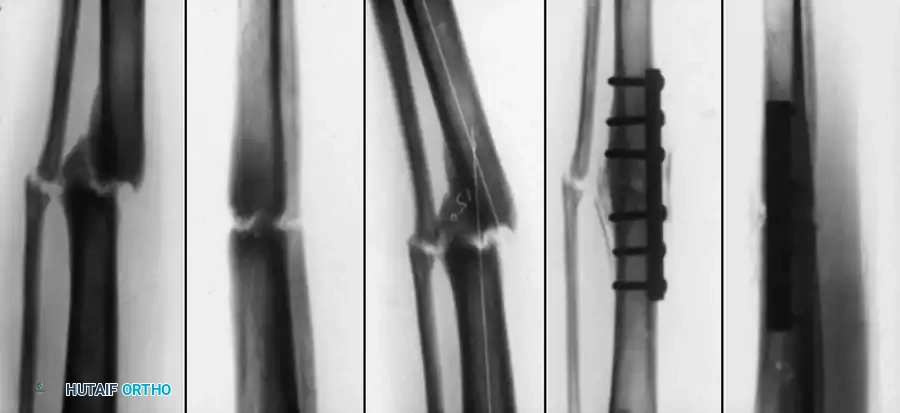

The "floating knee" describes an ipsilateral fracture of the femur and tibia, creating a flail knee joint. These are high-energy injuries often associated with polytrauma. The Letts classification (Types A through E) categorizes these based on whether the fractures are open or closed, and whether they involve the diaphysis or the metaphysis/epiphysis.

Fig. 33-172: A and B, Severe floating knee injury with midshaft fracture of femur, Salter-Harris type I fracture of distal femoral physis, and comminuted fracture of tibial shaft. C, After internal fixation of distal femoral physeal fracture with crossed pins and external fixation of fractures of femoral and tibial shafts.

The Bohn and Durbin classification system, modified by Arslan et al., further delineates these complex patterns:

* Type I: Double shaft fracture.

* Type II: One juxtaarticular fracture.

* Type IIIa: One epiphyseal fracture, one metaphyseal or diaphyseal fracture.

* Type IIIb: Both epiphyseal fractures (distal femur, proximal tibia).

* Type IV: Femur and/or tibia fracture at two distinct sites.